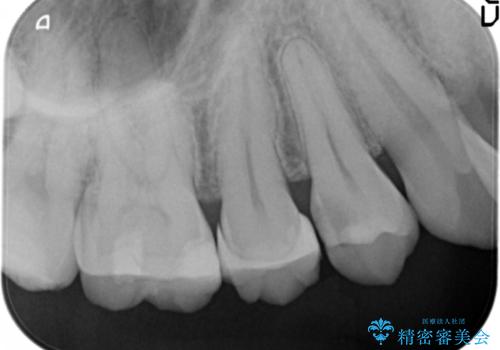

窩洞形態により選択するインレーの素材

- 定期検診を希望され来院、虫歯が発見されたため治療へと移行しました。

虫歯の大きさや残存歯質・窩洞形態によりゴールドやセラミックといった材質を選択することでより歯を削る量を少なくすると同時に強度も確保、長期的な予後を期待できるような治療を実践していきます。

セラミック・ゴールド共に化学的な変化が少なくインレー素材として理想的ですが、色調や強度・加工のしやすさ・最低限必要な厚み等の条件が異なります。

今回の治療では、虫歯を除去したのちより修復に適した素材を選択することで歯を削る量を可及的に少なくすることと、長期的な予後を期待できるような状態にすることができました。